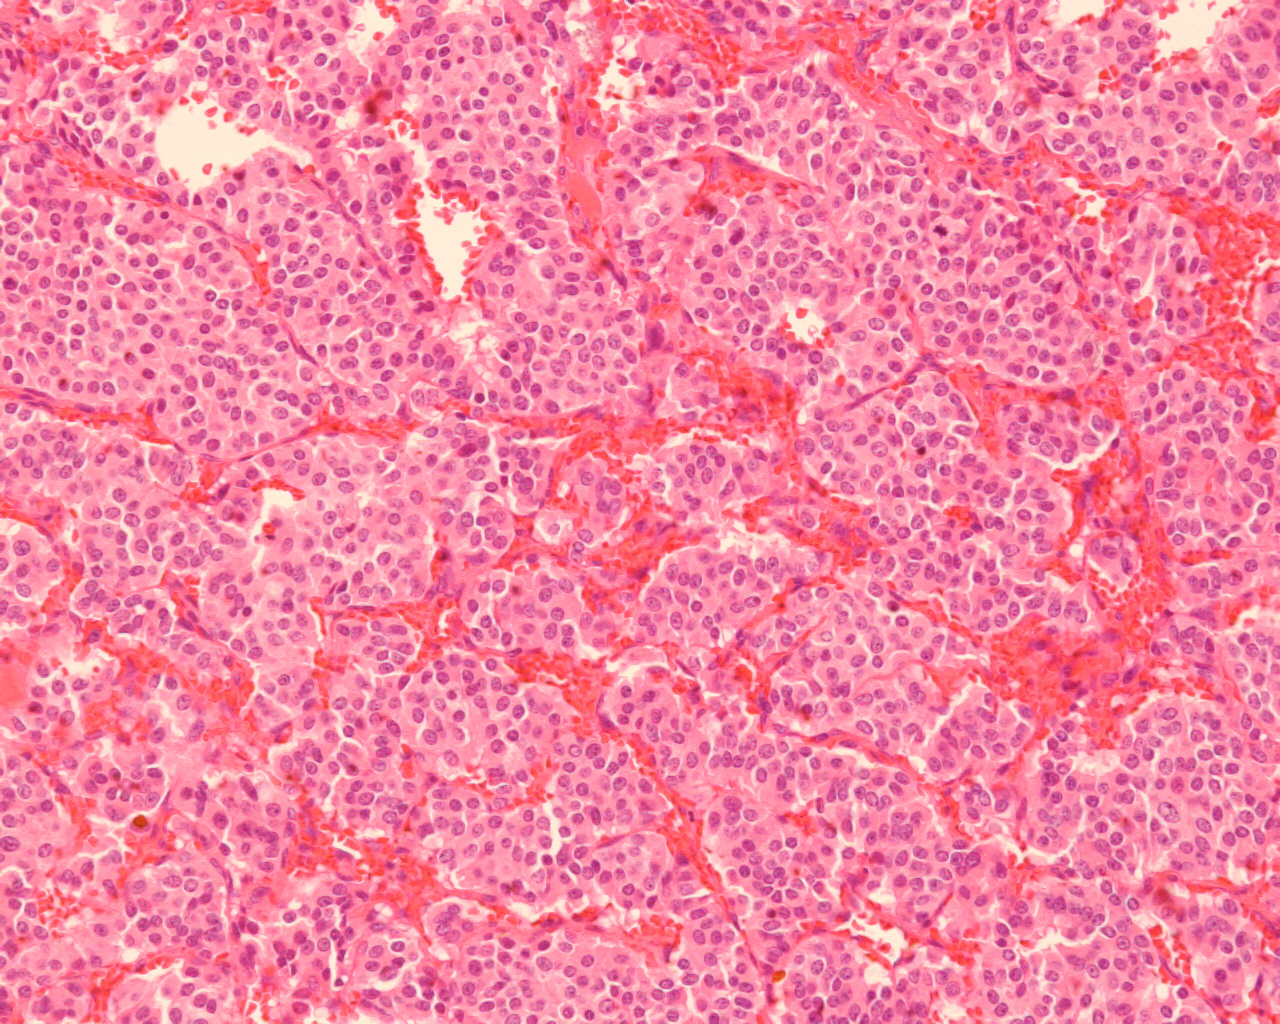

縦隔腫瘍にて迅速診断検査を施行。

組織診断: Carcinoid tumor of the thymus

Ki-67 synaptophysin